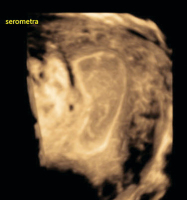

Ultraschall-Serometra

Abbildung 4: HyCoSy, die iatrogene Serometra: Links im Bild ist deutlich der Katheter sichtbar, mit dem das echoarme NaCl ins Cavum uteri eingebracht wird.